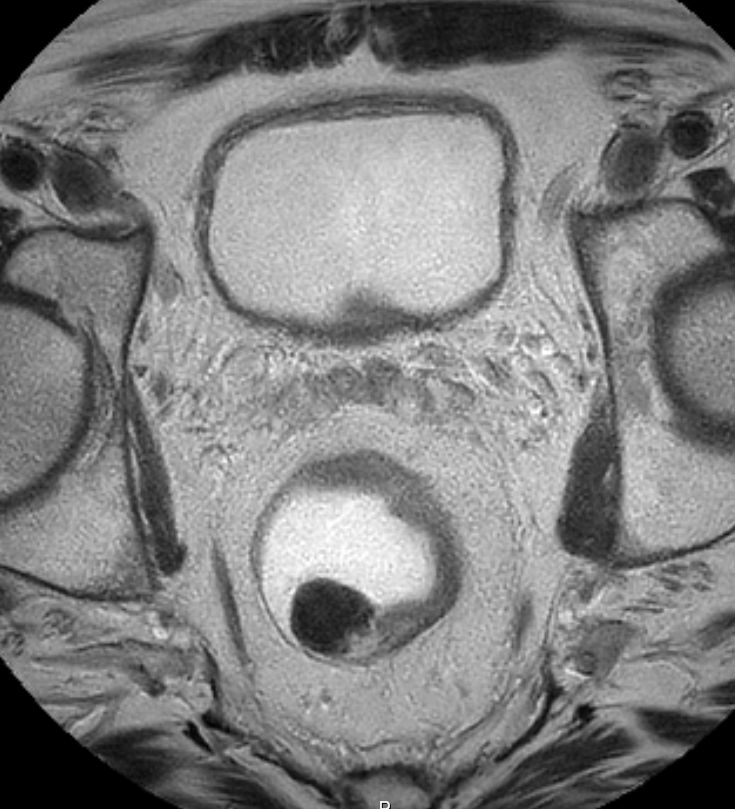

| MRT: T2 | 69-jähriger Mann mit mäßig differenziertem

Adenokarzinom bei 15 cm.![]() |

![]() |

![]() | |